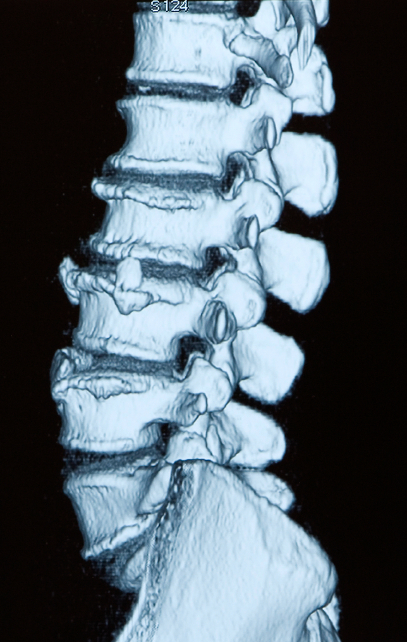

Degenerative Arthritide: - Non-inflammatory - MC involves weight bearing joints - Usually stiffens with rest and improves with activity - Complications include spinal stenosis and IVF encroachment

DJD aka Osteoarthritis

Radiographic signs: - IVD narrowing - Osteophytes - Endplate sclerosis

DJD in spine